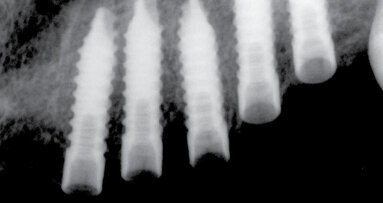

Zubní implantáty jsou skvělým přídavkem do repertoáru každého praktického zubního lékaře, jelikož nám umožňují nahradit ztracený zub bez ...